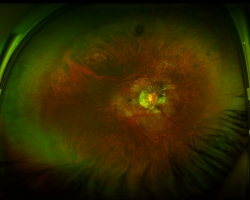

Rétinophotographies des deux yeux (optomap = photographies très grand champ)

- OD : rétine à plat d’une myope forte avec atrophie péripapillaire. Existence d’altération de l’épithélium pigmentaire avec cicatrice pigmenté de la macula (hors programme, explique l’absence de 10/10 OD)

- OG : décollement de rétine rhegmatogène sur déchirure en temporal au niveau d’une zone de fragilité rétinienne (palissade = hors programme)